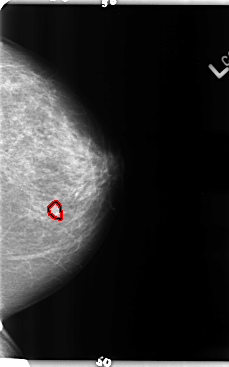

B_3158_1.RIGHT_MLO

LEFT_MLO LINES 4760 PIXELS_PER_LINE 2760 BITS_PER_PIXEL 12 RESOLUTION 50 OVERLAY

FILE: B_3158_1.LEFT_MLO.OVERLAY

TOTAL_ABNORMALITIES 1

ABNORMALITY 1

LESION_TYPE MASS SHAPE LOBULATED MARGINS CIRCUMSCRIBED-OBSCURED

ASSESSMENT 3

SUBTLETY 2

PATHOLOGY BENIGN

TOTAL_OUTLINES 1

BOUNDARY